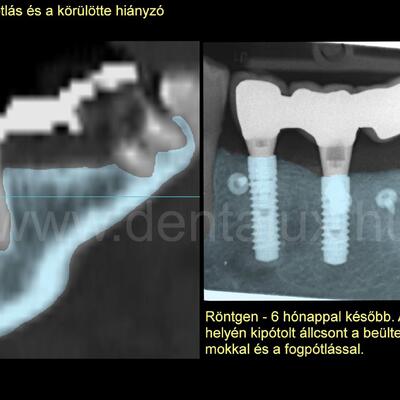

Magyarországon a csontritkulás vagy orvosi nevén oszteoporózis népbetegségnek számít. Az ilyen betegségben szenvedők elégtelen csontminőséggel, műtét után egyes csontritkulásra szedett gyógyszerek miatt a gyógyulás zavarával számolhatnak. Emiatt a foghiány modern ellátásából, úm. fogbeültetés és csontpótlás, sokszor kiszorulnak. Ennek pedig rosszabb életminőség, az önbecsülés csökkenése lehet a következménye. Mindez csupán amiatt, mert csontritkulásban szenvednek. Az ő számukra jó hír és az ilyen betegek ellátásában mérföldkő egy nemrég közzétett tudományos munka. Kimutatták, hogy az ilyen betegek foghiányát megfelelő implantátummal ellátva a hosszútávú sikeresség nem rosszabb az egészségesekénél. Ez számunkra is nagy öröm. Mivel egybeesik az ilyen pácienseink ellátásával szerzett hosszútávú tapasztalatunkkal. Vagyis kijelenthető: rendelkezésünkre áll olyan speciális implantátum, amivel a fogbeültetés és csontpótlás a csontritkulásban szenvedők számára hosszútávon sikeres lehet. Foghiány esetén az oszteoporózissal rendelkezőknek ma már nem kell lemondani a fogbeültetés lehetőségéről és alacsonyabb életminőséggel élni. (A hivatkozott vizsgálat nem saját csont felhasználásával végzett csontpótlást és speciális felszíni kialakítású fogászati implantátumot vizsgált. Ilyen a Straumann Roxolid SLActive).